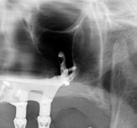

Este caso clínico es un premolar que tiene 3 conductos: sabemos que 2 de ellos son en la raíz vestibular, y

en el CBCT podemos apreciar a qué longitud del conducto se produce la bifurcación (Figura 10)

Debido a la gran curvatura que se produce en la bifurcación, tenemos que precurvar los instrumentos manuales y rotatorios, para facilitar que los instrumentos alcancen la LT (Figura 11). Terminamos el conducto mesiovestibular y palatino en conicidad .06 y el disto-vestibular en .04 debido al riesgo que pensamos que correríamos si hacemos una secuencia más amplia.

Valorando cada uno de los factores que hemos descrito anteriormente, podemos decidir, para el éxito de este tratamiento, una combinación: secuencia más progresiva; trabajar 3 ciclos por conducto para los instrumentos de preinstrumentación y conformación; eliminación de interferencias coronales con puntas ultrasónicas

e instrumento 25.09; terminar en conicidad .04/.06 según la dificultad del conducto; combinar movimiento continuo y alterno; y usar instrumentos precurvados de manera manual previo al rotatorio. Todo esto hará que resolvamos este caso clínico de manera satisfactoria (Figura 12). ●

Figura 10. Estudio Radiográfico en 2D y 3D del caso clínico. Figura 11. Secuencia operatoria que realizamos en cada uno de los conductos. Figura 12. Secuencia realizada para la obturación con onda continua.